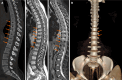

Results: Spine computed tomography (CT) scans were performed in 192 of 238 patients with a suspected spinal injury, 42 of whom also had an magnetic resonance imaging (MRI). In 86 of 192 patients (44.79%; M:F = 33:53) a spinal fracture was detected on CT and in 33 of 42 patients (78.57%; M:F = 20:13) a spinal injury was found on MRI. Of the 86 patients in whom vertebral injury was detected, fractures were detected in the Denis-B group in 33, Denis-C in 4, Denis-D in 20 and Denis-E in 11 patients. Among the vertebral bodies: 40 "compression fractures", 17 "burst fractures", 5 "translational dislocation fractures", 5 "flexion-distraction fractures" and 58 "prolonged forced fetal posture fractures" were detected. In addition, isolated transverse or spinous process fractures were found in eighteen vertebrae.

Conclusion: Our study highlights the prevalence and diverse spectrum of spinal injuries following the February 6, 2023 twin earthquakes in Turkey underscoring the urgent need for effective management strategies in similar disaster scenarios, and emphasizing the "prolonged forced fetal posture" damage we encountered in earthquake victims who remained under the collapse for a long time.